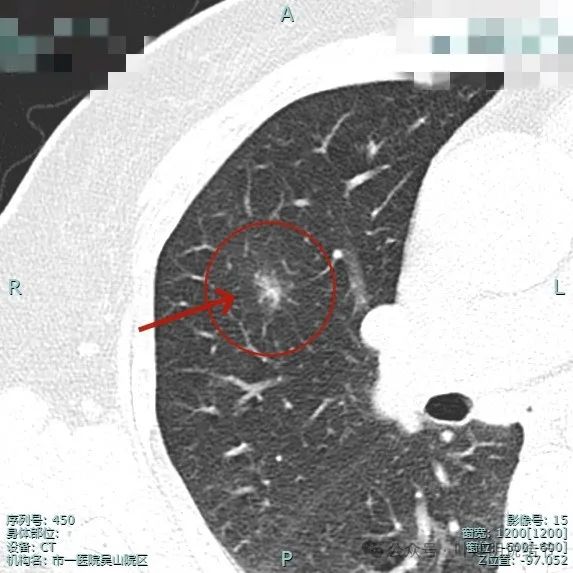

这是2024年4月靶重建时平扫的影像,病灶大小无明显增大,但密度显得较高。

再来看靶重建的影像:

病灶整体显得模糊,但灶内密度不均,有偏实性成分,边缘毛糙,似有小血管走向病灶,轮廓较清楚,瘤肺边界欠清。